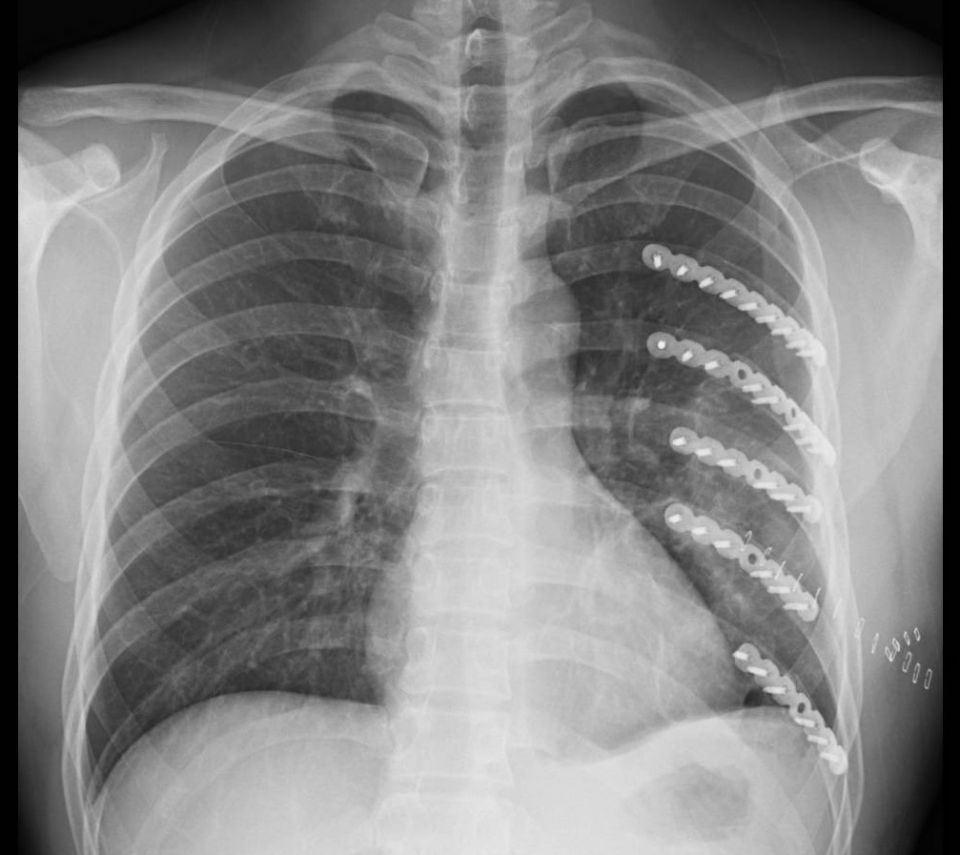

微創肋骨手術後的x光片。(記者葉靜美翻攝)

為此,彰化醫院胸腔外科主任林聿騰為李政錡施以微創肋骨手術,他表示,雖然傷者左胸肋骨幾乎全斷,範圍很大,但以最新的設備,配合3D胸廓重組影像的精準定位,用最小傷口的微創手術進行復位,再以肋骨專用的鈦合金板固定,將傷口縮小到只有9公分。